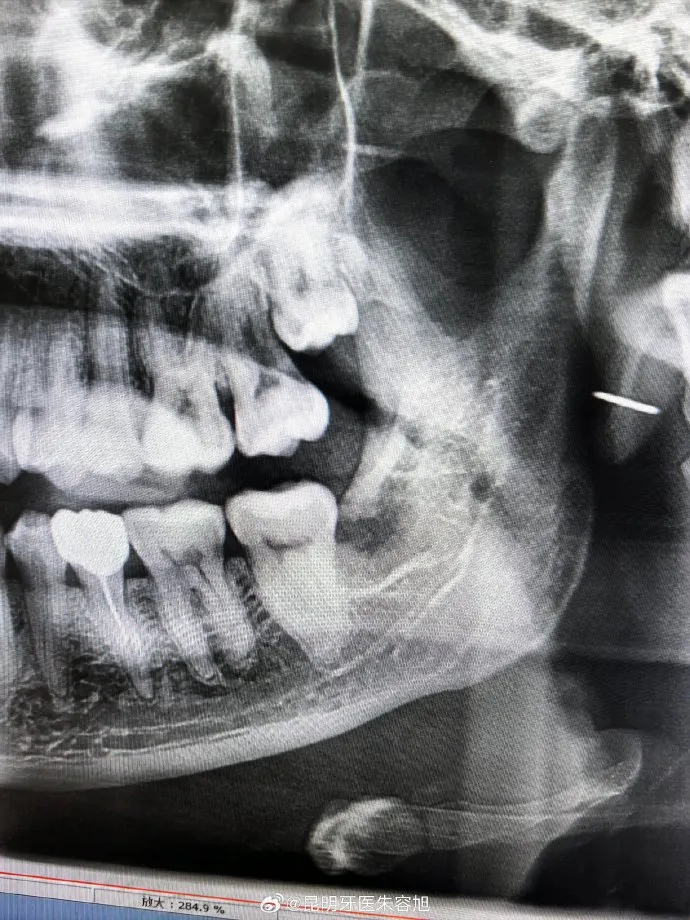

- **Technology** – Look for clinics using advanced imaging and surgical tools for better accuracy.